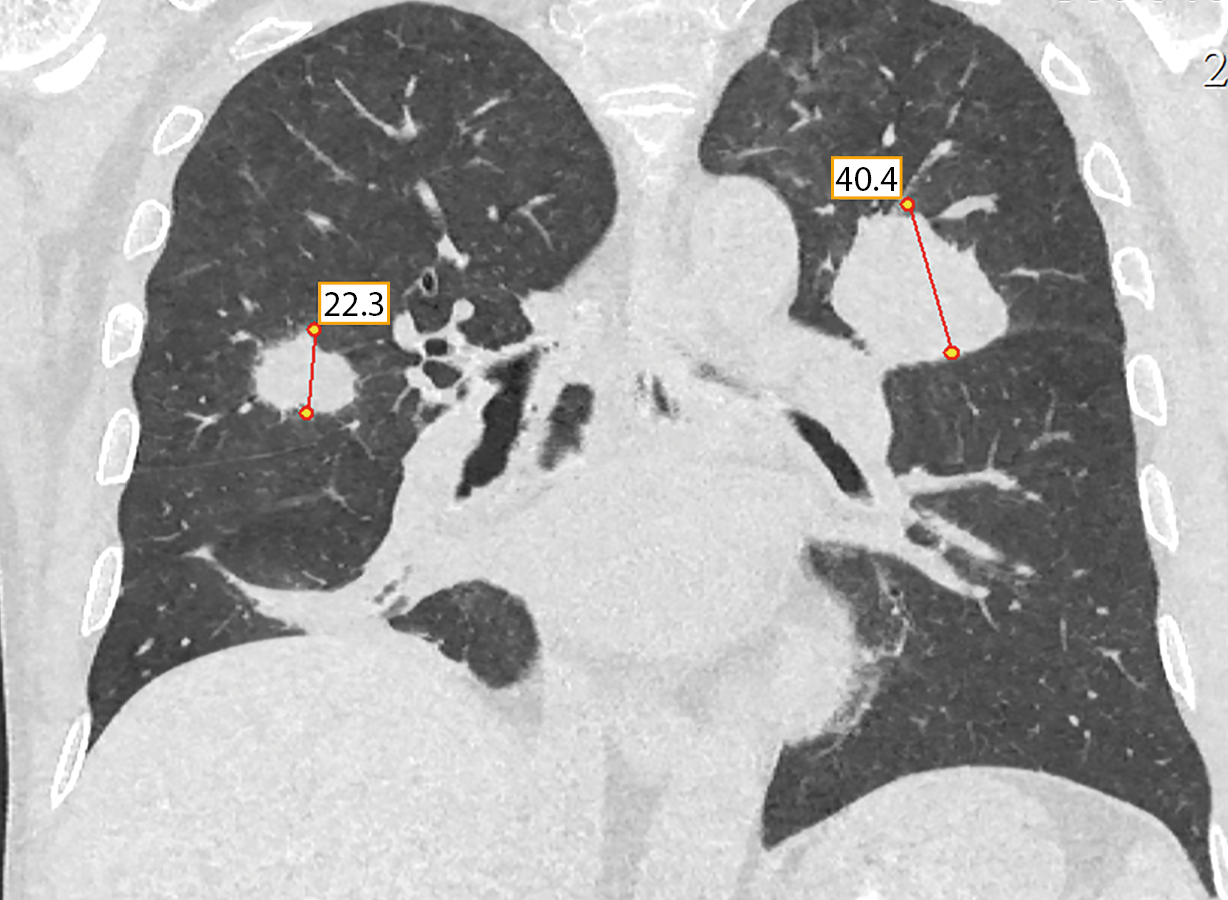

При КТ грудной клетки свежих инфильтративных изменений не выявлено. В S3 левого легкого — уплотнение легочной ткани вытянутой формы — 2,5х1,8 см, накапливающее контрастное вещество (рис. 3). Лимфоузлы легких и корней легких не увеличены, структурно не изменены.

Рисунок 3. КТ органов грудной клетки: в S3 левого легкого уплотнение легочной ткани вытянутой формы — 2,5х1,8 см, накапливающее контрастное вещество.

При контрольной КТ грудной клетки через 20 дней выявлено резкое увеличение размеров новообразования в S3 левого легкого с 2,5 см до 4,4 см, с активным накоплением контрастного вещества. В S3 правого легкого появилось новое образование 2,3х1,2 см со схожими характеристиками (рис. 6).

Рисунок 6. Контроль КТ грудной клетки через 20 дней: увеличение размеров новообразования в S3 левого легкого с 2,5 см до 4,4 см, накапливающее контраст, появление нового образования в S3 правого легкого 2,3х1,2 см.